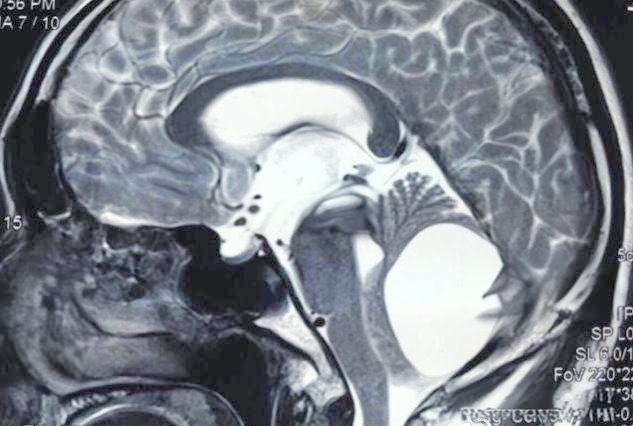

大枕大池及其鉴别诊断详解